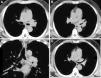

A-C) TC diagnóstica en la que se observa un marcado engrosamiento del bronquio principal izquierdo, que se extiende al bronquio del lóbulo superior homolateral, con masa de tejido blando que protruye en la luz del bronquio lobar superior. D) TC de control 2 meses postratamiento, en la que se evidencia una disminución del engrosamiento de la pared del bronquio principal izquierdo y el bronquio del lóbulo superior, y desaparición de la masa de partes blandas que ocupaba la luz del bronquio lobar superior izquierdo.

Presentamos el caso de un paciente varón de 52 años, diagnosticado de leucemia aguda mielomonocítica en tratamiento con quimioterapia de segunda consolidación. Ingresó por fiebre y tos con expectoración. Estaba en tratamiento con colistina inhalada desde hace un mes, por colonización de la vía respiratoria por Pseudomonas aeruginosa multirresistente. Se decidió suspender la quimioterapia e iniciar estudio diagnóstico. En la radiografía de tórax no se demostraron alteraciones significativas y en el hemograma destacaba hemoglobina 10,8g/dl, leucocitos 7,7×103μ/l y 69% de neutrófilos. Se realizó un nuevo cultivo de esputo que fue positivo para Pseudomonas aeruginosa multirresistente, por lo que se continuó el tratamiento con colistina. Ante la persistencia de la sintomatología, se realizó una tomografía computarizada torácica (TC) en la que se observó engrosamiento parietal de la carina y del bronquio principal izquierdo, con extensión al bronquio del lóbulo superior y parcialmente al bronquio del lóbulo inferior homolateral con masa de tejido blando que protruye en la luz del bronquio lobar superior (fig. 1 A-C). El parénquima pulmonar no presentaba alteraciones (fig. 1).

En el contexto clínico de paciente inmunodeprimido el primer diagnóstico a considerar fue una infección fúngica (aspergilosis, candidiasis o mucormicosis). Se llevó a cabo una fibrobroncoscopia, donde se apreciaron membranas blanquecinas en la tráquea y en ambos bronquios principales. Se tomaron biopsias, demostrando la presencia de membranas fibrino-inflamatorias y fragmentos de mucosa bronquial con metaplasia escamosa madura y neovascularización, sin evidencia de malignidad. En el cultivo de las muestras se aisló Aspergillus fumigatus; se inició tratamiento con voriconazol, con desaparición progresiva de la fiebre y tos. En la TC de control 2 meses postratamiento se evidenció disminución del engrosamiento de la pared traqueobronquial (fig. 1 D).